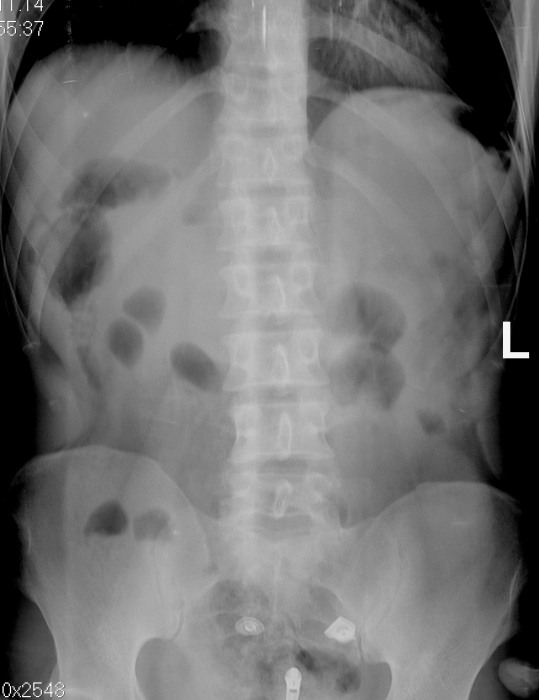

С подозрением на проникающее ранение направлен на рентгенографию брюшной полости. Суицид.

А где рана? Слева под куполом как бы есть воздух. Но не утверждаю.

Рана центрально, по белой линии живота, на 3 см. выше пупка.

Есть пневмоперитонеум

симптом серпа как то неубедителен, а вот тонкокишечные арки свидетельствуют о непроходимости, видимо из-за раздражения брюшины кровью

Положил пациента на левый бок на две минуты...

теперь все точки расставлены над i.

Кстати, первый снимок стоя или лежа? в любом случае воздух под диафрагмой слева такой формы быть не может, если находится интрависцерально.

Я про непроход. Может это рефлекторные "сторожевые" петельки вылезли в ответ на брюшную катастрофу. Но вот так, по двум невнятным петлям, без четких симптомов пат.уровней, весов и пружины ставить непроход...?

при брюшной катастрофе как вариант спастическая динамическая в ответ на раздражение брюшины, сначала ведь именно арки появляются а уж при прогрессировании процесса и уровни жидкости. я так себе это все представляю.

После проведения рентгенологического исследования хирурги пошли на ревизию брюшной полости - повреждение сальника, проникающее ранение желудка.